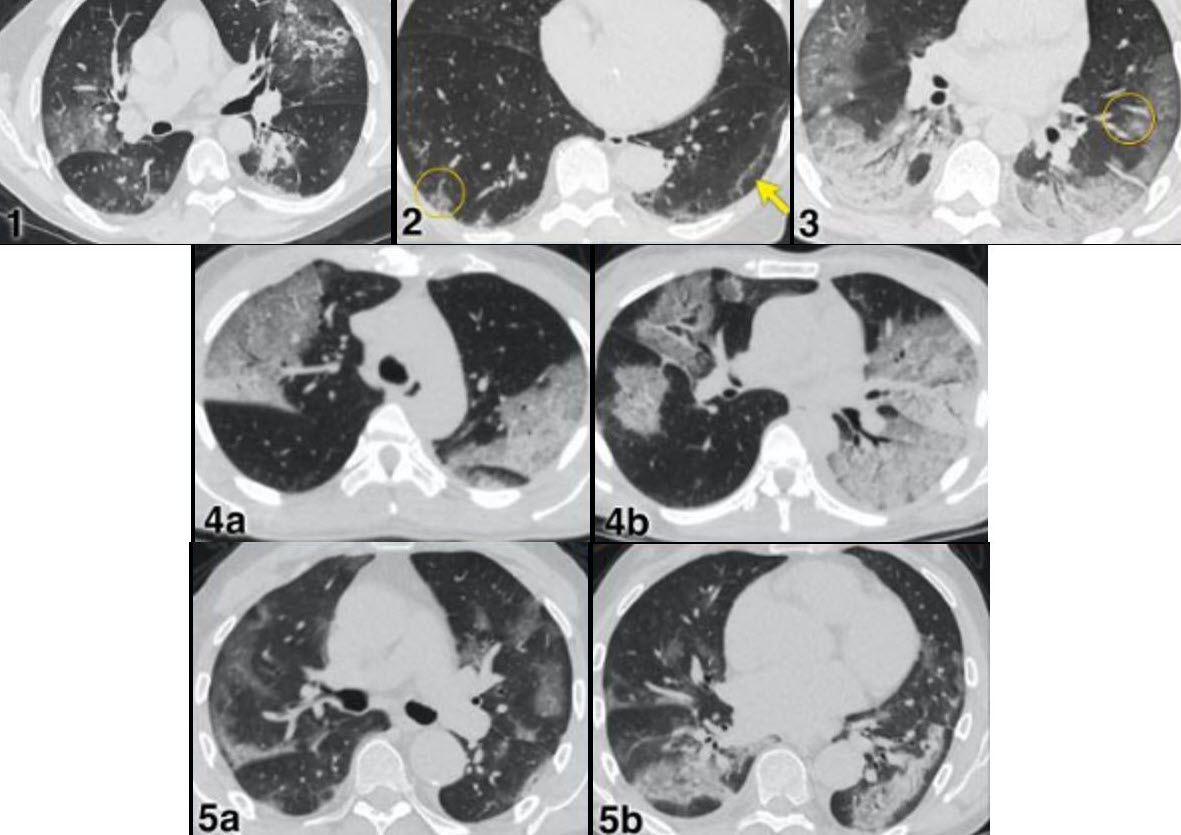

Một trường hợp được báo cáo là bé gái 15 tuổi (ở Bắc Ninh), vào viện trong tình trạng sốc, hôn mê, suy hô hấp. Kết quả chụp CT cho thấy phù não, hình ảnh tổn thương lan tỏa ở phổi. Cấy máu dương tính với tụ cầu vàng. Bệnh nhân may mắn được cứu sống sau nhiều ngày hồi sức tích cực.

Hình ảnh CT cho thấy tổn thương phổi lan tỏa do sốc nhiễm khuẩn tụ cầu vàng.